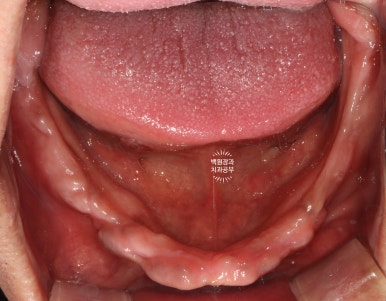

이를 뽑고나서 임시틀니를 만들어드렸고, 위에서 보는 사진은 이를 제거 하고 약 1.5달 뒤 사진입니다.

잘 보시면, 이를 뽑고나서 잇몸이 잘 아물어 단단한 잇몸이 되어 있는 것을 보실 수 있으실거에요.

보통, 많은 양의 뼈이식을 해야할 경우 상부에 단단한 잇몸이 필요하기 때문에 적어도 1.5달 정도는 기다려야 합니다.